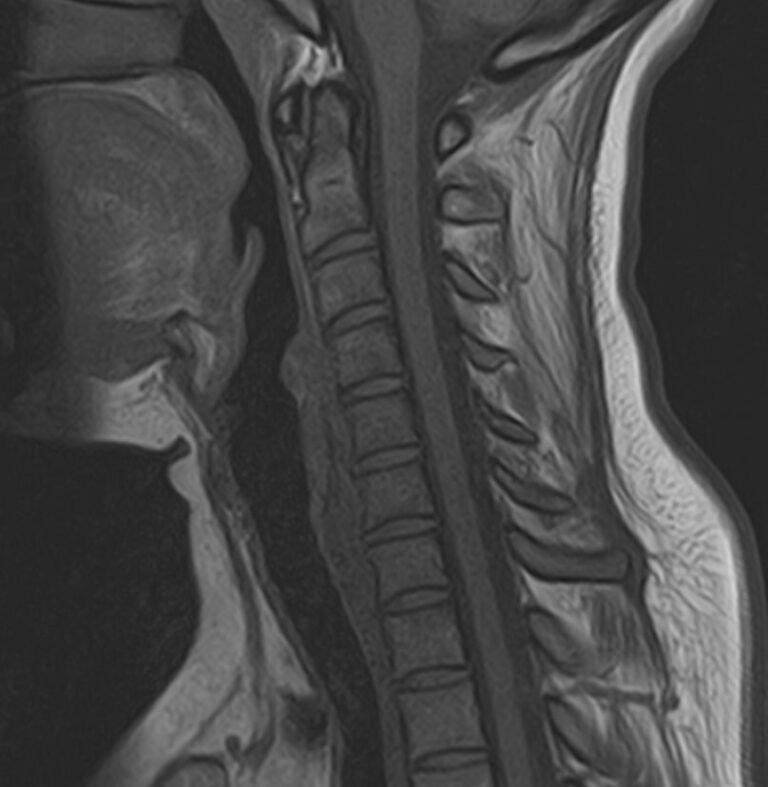

Шейный отдел позвоночника — это самый подвижный сегмент позвоночного столба, который испытывает повышенные нагрузки, подвержен травмам и развитию различных заболеваний. В эту анатомическую область входит 7 верхних позвонков, спинной мозг с отходящими от него нервными корешками.

Кроме того, в области шеи проходят крупные кровеносные сосуды, кровоснабжающие все структуры головного мозга и мягких тканей головы. К ним относятся плечеголовной ствол, сонные и позвоночные артерии, которые далее в полости черепа соединяются между собой в Виллизиев круг. Это анатомическое образование позволяет компенсировать мозговой кровоток при патологических состояниях.

Часто различные нарушения в шейном отделе позвоночника приводят к ухудшению кровоснабжения головного мозга. Опухоли и дегенеративно-дистрофические заболевания шейного отдела позвоночника могут нарушать работу головного мозга. Атеросклеротические бляшки в сосудах шеи могут стать причиной преходящих нарушений мозгового кровообращения (транзиторных ишемических атак) и привести к развитию инсульта. Поэтому важно в комплексе детально визуализировать эти анатомические структуры вместе с оценкой состояния кровеносной системы головы и шеи.

Сканирование проводится на современном высокопольном магнитно-резонансном томографе закрытого типа TOSHIBA VANTAGE TITAN 1,5 Тесла. Магнитно-резонансный томограф производит послойное сканирование исследуемой зоны в разных плоскостях, затем при помощи компьютерных программ преобразует полученные данные в трехмерные изображения. При этом кровеносная система реконструируется как вместе с окружающими тканями, так и отдельно без них.

• остеохондроз, спондилоартроз, спондилез, межпозвонковые грыжи, унковертебральный артроз, сколиоз, усиленный или выпрямленный лордоз как нарушение статической функции позвоночника, травмы, аномалии позвоночника.